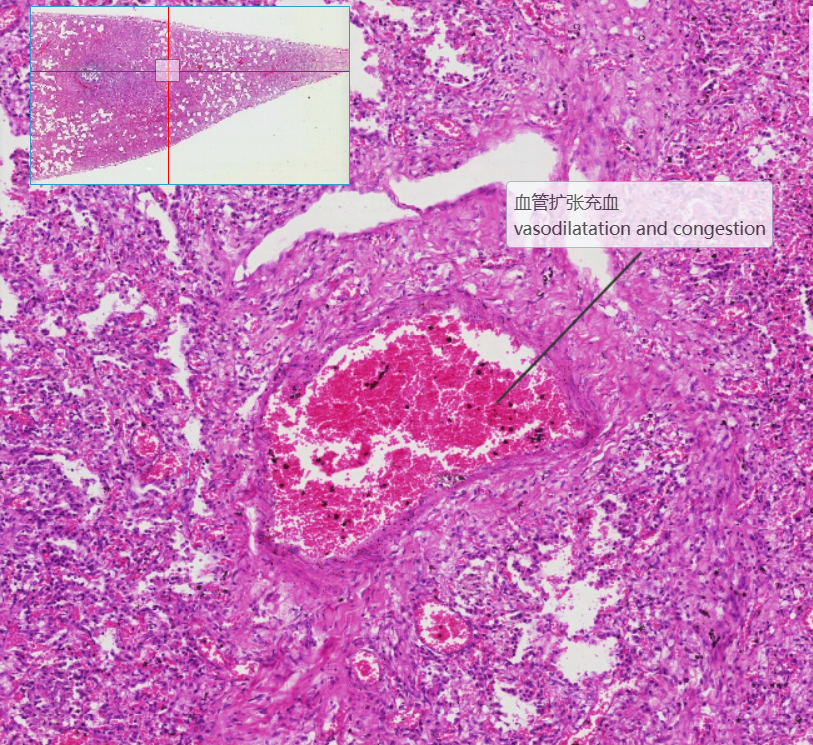

2 肺脓肿